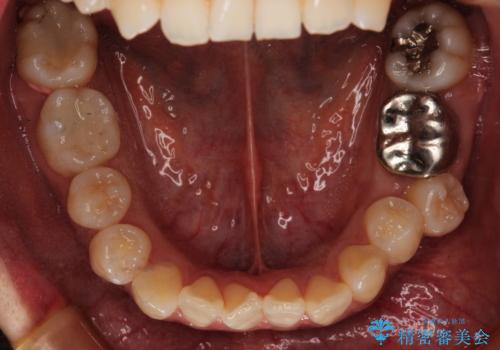

ハーフリンガル抜歯矯正 八重歯を改善する

- 小臼歯4本抜歯によるハーフリンガル・ワイヤー矯正を計画した。

シビアな八重歯がきれいに歯列にはいることにより、笑った時の印象などもかなり大きく変わります。